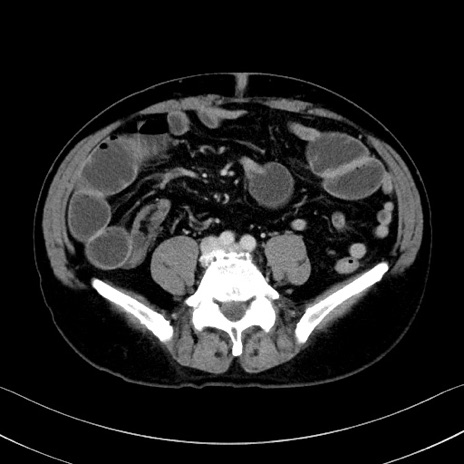

症例35(横断像)

【症例】70歳代 男性

【主訴】腹部膨満、嘔吐

【現病歴】昨日より腹部膨満感出現。本日増悪し、仙痛出現。嘔吐あり、受診。

【既往歴】糖尿病、胆摘後

【身体所見】BP 149/80mmHg、HR 74/min、BT 35.9℃、腹部:膨満、軟、圧痛なし。腸雑音減弱あり。上腹部正中切開瘢痕あり。

【データ】WBC 13500、CRP 1.72